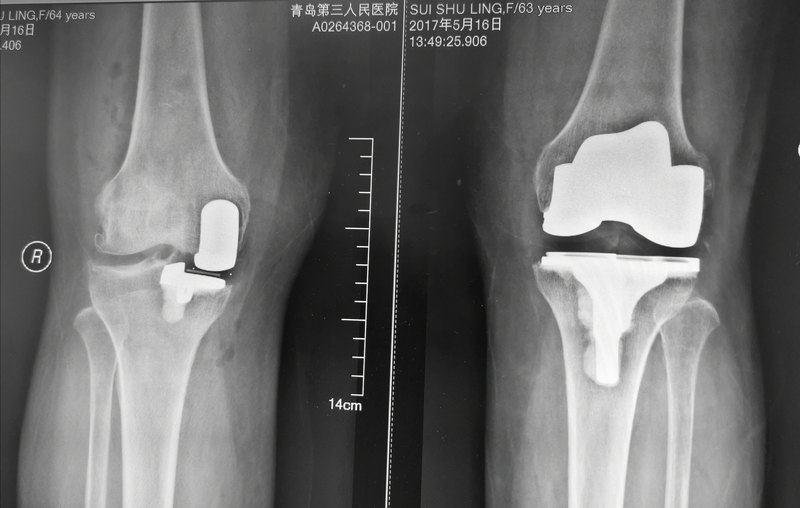

正常的膝關(guān)節(jié)表面有很多的軟骨,就是老百姓說(shuō)的脆骨,上面沒(méi)有神經(jīng),活動(dòng)的時(shí)候比較光滑,病人不會(huì)感覺(jué)到疼痛。當(dāng)出現(xiàn)膝關(guān)節(jié)的病變,軟骨磨損了,病人會(huì)出現(xiàn)癥狀會(huì)疼痛,因?yàn)檫€是比較輕微的,到醫(yī)生那里就診醫(yī)生會(huì)做一些保守治療。當(dāng)病人疾病進(jìn)一步發(fā)展,軟骨完全磨損了,正常的膝關(guān)節(jié)需要活動(dòng)就是骨頭和骨頭進(jìn)行摩擦,病人很疼痛,可能產(chǎn)生骨的變形,這時(shí)候就需要做手術(shù)治療。人工關(guān)節(jié)置換手術(shù)就是用金屬來(lái)替代原來(lái)軟骨的位置,當(dāng)中有一個(gè)超高分子的聚乙烯。做完一個(gè)人工膝關(guān)節(jié)置換以后,正?;顒?dòng)就沒(méi)有骨與骨的接觸,保持正常功能,這就是人工關(guān)節(jié)置換手術(shù)的目標(biāo)。最重要是病人不痛,希望維持到正常的活動(dòng)度,以此達(dá)到維持正常的日常生活,以前可以干什么,希望經(jīng)過(guò)康復(fù)以后還可以繼續(xù)做。 以前把人工關(guān)節(jié)置換手術(shù)定義為五十歲以上老人的手術(shù),第一個(gè)原因是發(fā)病率一般是老年病人居多,第二個(gè)原因是受材料的限制,我們認(rèn)為人工關(guān)節(jié)置換手術(shù)由于是假的東西,不會(huì)再生,跟正常人的關(guān)節(jié)不一樣,軟骨可以再生的,而這個(gè)磨損之后就沒(méi)有了。由于當(dāng)時(shí)材料的限制,只能用十年或者十五年,年份過(guò)了之后就磨壞了,需要進(jìn)行第二次手術(shù),比第一次手術(shù)困難得多,而且并發(fā)癥也多一些。所以,就把手術(shù)定位在老年病人當(dāng)中。事實(shí)上隨著材料的改進(jìn),假體的設(shè)計(jì)包括醫(yī)生的技術(shù)越來(lái)越高,人工關(guān)節(jié)置換有年輕化的趨勢(shì),有很多年紀(jì)比較輕的,可以通過(guò)手術(shù)來(lái)恢復(fù)正常生活。